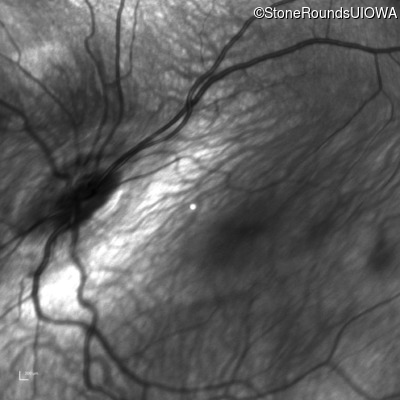

Infrared Fundus Photograph - Right - 10/125

Exemplar

Infrared Fundus Photograph - Left - 10/200